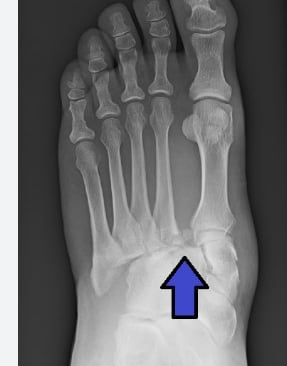

Fracture guide